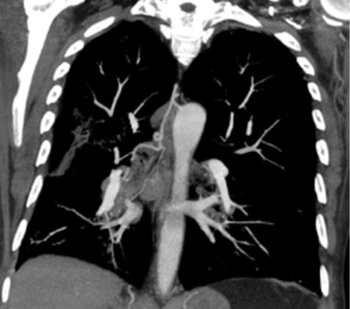

Fallbeispiel Bronchialkarzinom – Spiralembolisation eines blutenden Bronchialkarzinoms (Lungentumor)

CT des Thorax (coronare MPR): Typisch gewundener Verlauf der kräftigen rechten Bronchialarterie, die den Lungentumor versorgt. (MPR=MultiPlanare Reformation)